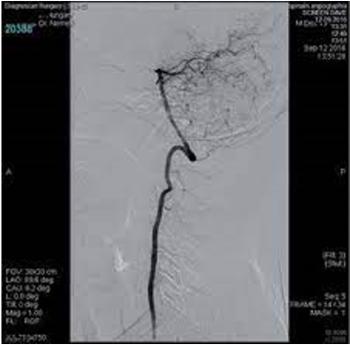

IV.2.5.7. Intervenciós vagy invazív röntgent (DSA)